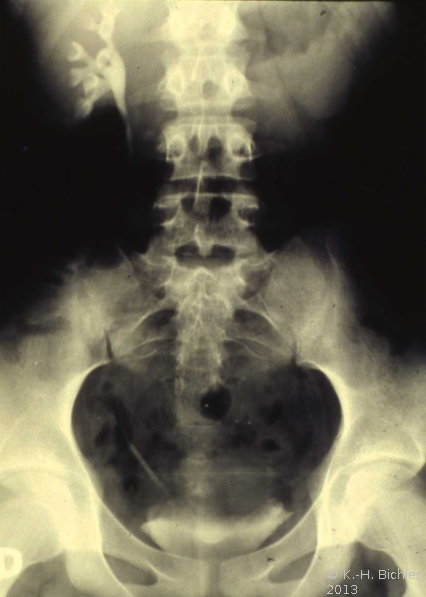

Das Ausscheidungsurogramm ergab eine stumme Niere links (Abbildung 18c). Die retrograde Sondierung zeigte eine deutlische Kompression des Harnleiters sowie eine verkleinerte Niere links mit destruierten Kelchen (Verplumpung) (Abbildung 18d).